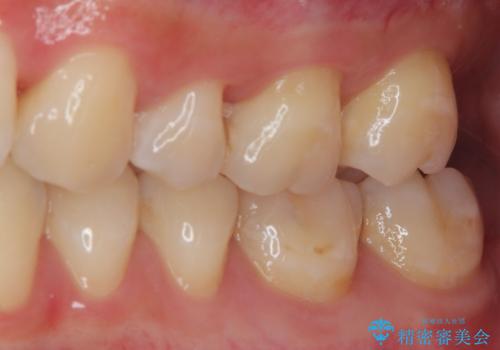

奥歯がしみる 保険の詰め物をセラミックインレーに

- 奥歯が食事の度にしみてしまうとのことで来院された患者様です。

目視やレントゲン写真からは、以前処置された部分に大きな問題は認められませんでしたが、冷たい風をかけると強い痛みを感じる状態でした。

患者様と相談の上、詰め物を全て外した上でむし歯があるかどうかを確認し、セラミックインレーで精密な修復治療を行うこととしました。

精密な型取りと、ラバーダム防湿下での接着操作により、歯と詰め物の隙間を最小限にとどめることができ、処置後はしみる症状が一切なくなりました。